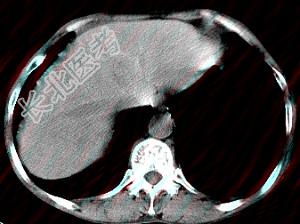

- 单项选择题男,40岁有血吸虫感染史,腹胀不适,食欲减退,CT扫描所见如图,最可能的诊断是 ( )

A、肝炎后肝硬化

B、血吸虫后肝硬化

C、酒精性肝硬化

D、胆汁性肝硬化

E、脂肪肝